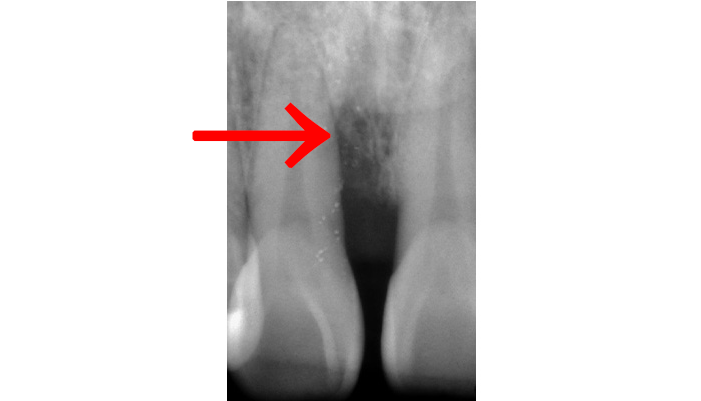

症例1

治療前

治療の経緯

患者様は「他院で神経を取るしかないと言われたが、できれば神経を残したい」とのご希望で来院されました。初診時には冷たいものがしみる症状はありましたが、自発痛や打診痛はなく、診査の結果、歯髄を温存できる可能性があると判断しました。

治療では拡大視野下でむし歯の感染部分を正確に除去し、MTAを用いた歯髄温存療法を実施しました。

| 主訴 | 歯に穴が空いた |

|---|---|

| 治療期間 | 1ヶ月 |

| 治療費 | ¥33,000 |

| 治療内容 | むし歯が大きく、神経を残す治療(歯髄温存療法)を行い、神経を残しダイレクトボンディングにて修復しました。 |

| 治療のリスク | 治療後に痛みが出ることがあります。また、痛みが強くでる場合は神経を取る治療に移行することもあります。 |